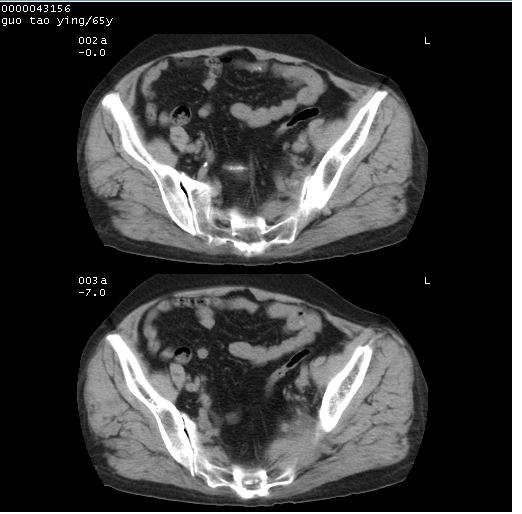

以下是引用黑白光影在2008-1-30 13:22:00的发言:[br]支持左耻骨骨折。[br]未见骶骨骨质明确破坏改变。[br]经楼主提示(勿局限于外伤)。考虑为右侧腹股沟直疝。[br][br][br][br]